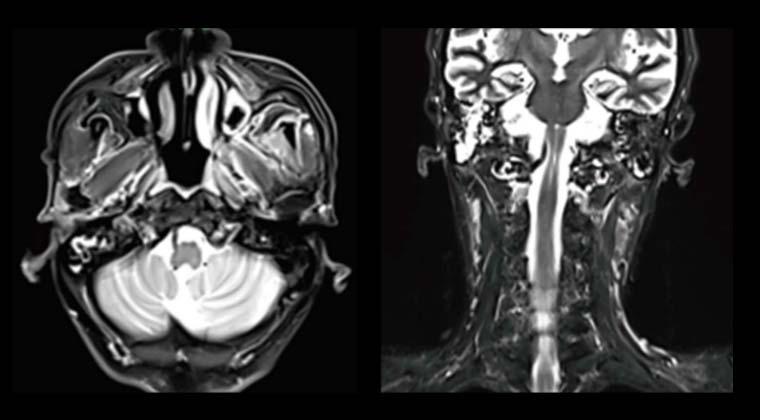

② Случай 2:

Пациентка, 76 лет

Диагноз «рак носоглотки» был поставлен 5 лет назад; стандартная химиолучевая терапия не проводилась, лечение осуществлялось самостоятельно. Месяц назад головные боли стали прогрессирующими и невыносимыми, сопровождались опущением левого века и снижением слуха.

Пациентка и семья попросили облегчить симптомы и уменьшить боль, отказавшись от химиотерапии. Была проведена паллиативная лучевая терапия локального очага опухоли. Опухоль оказывала давление на продолговатый мозг, поэтому была назначена доза 50 Гр / 25 фракций.

После 7 сеансов лучевой терапии опухоль значительно уменьшилась (на изображении область опухоли обозначена красной сплошной линией), головная боль облегчилась. У пациентки повысилась уверенность в лечении. План лучевой терапии был скорректирован для облучения шейной зоны лимфатического дренажа, и в итоге локальная опухоль получила суммарную радикальную дозу 70 Гр.

До лечения

После 7 сеансов лучевой терапии